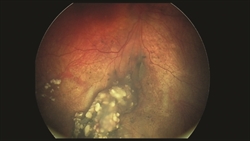

Figure 2: Ophthalmoscopy and photographs during examination reveal a large tumor with subretinal fluid that encompasses the eye. (Photo courtesy of G. Baker Hubbard, MD) |

Figure 3: This is the patient’s eye after treatment with 2 rounds of intra-arterial chemotherapy, along with additional laser photocoagulation of the tumor. The tumor has responded well to treatment. (Photo courtesy of G. Baker Hubbard, MD) |